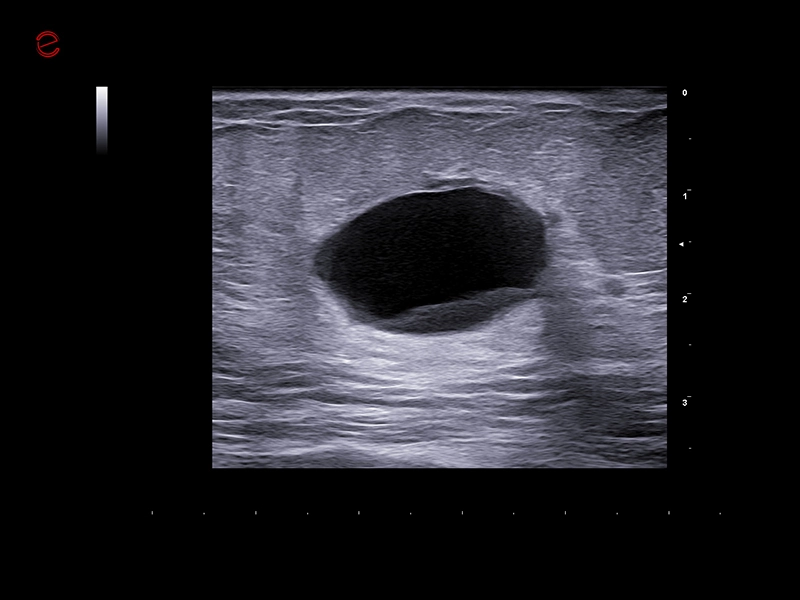

IDEAL FOR A VARIETY OF CLINICAL APPLICATIONS

High-quality imaging on-the-go

A compact and dependable partner, the MyLab™C25 is designed to support your daily practice with ease, providing high-quality imaging for confident diagnostics every time. With MyLab™C25 and its wide range of probes, we provide you with the ability to perform examinations in a broad variety of clinical applications such as general imaging, superficial scanning, cardiology, vascular, gynecology and obstetrics